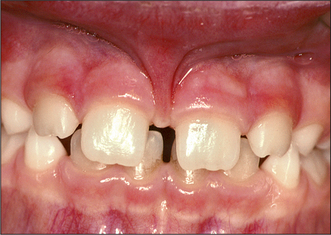

1. The tooth shown in Fig 12.16 is unerupted, asymptomatic and impacted.

(a) At what age does this tooth most frequently erupt?

(b) Describe three possible sequelae of leaving this tooth in situ.

(c) How could the position of the tooth be determined more accurately before surgery?

Fig. 12.16 See question 1.